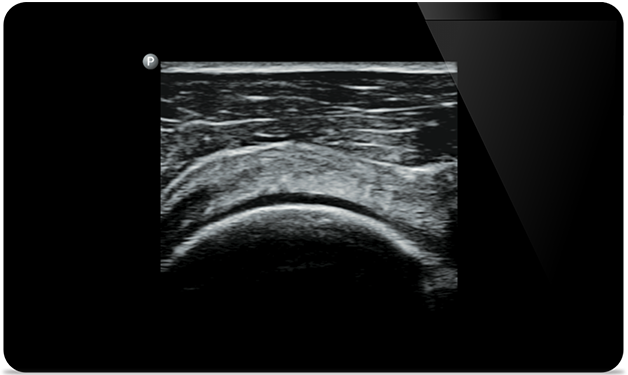

Start treatment with an accurate diagnosis

Lumify helps you see the fine details in muscles, joints, ligaments, tendons and cartilage to make a more accurate diagnosis of injuries.

Get the clarity of larger ultrasound systems with Lumify

SonoCT reinforces real tissue imaging while eliminating random artifacts. This technology produces images superior to conventional imaging in up to 94% of patients.